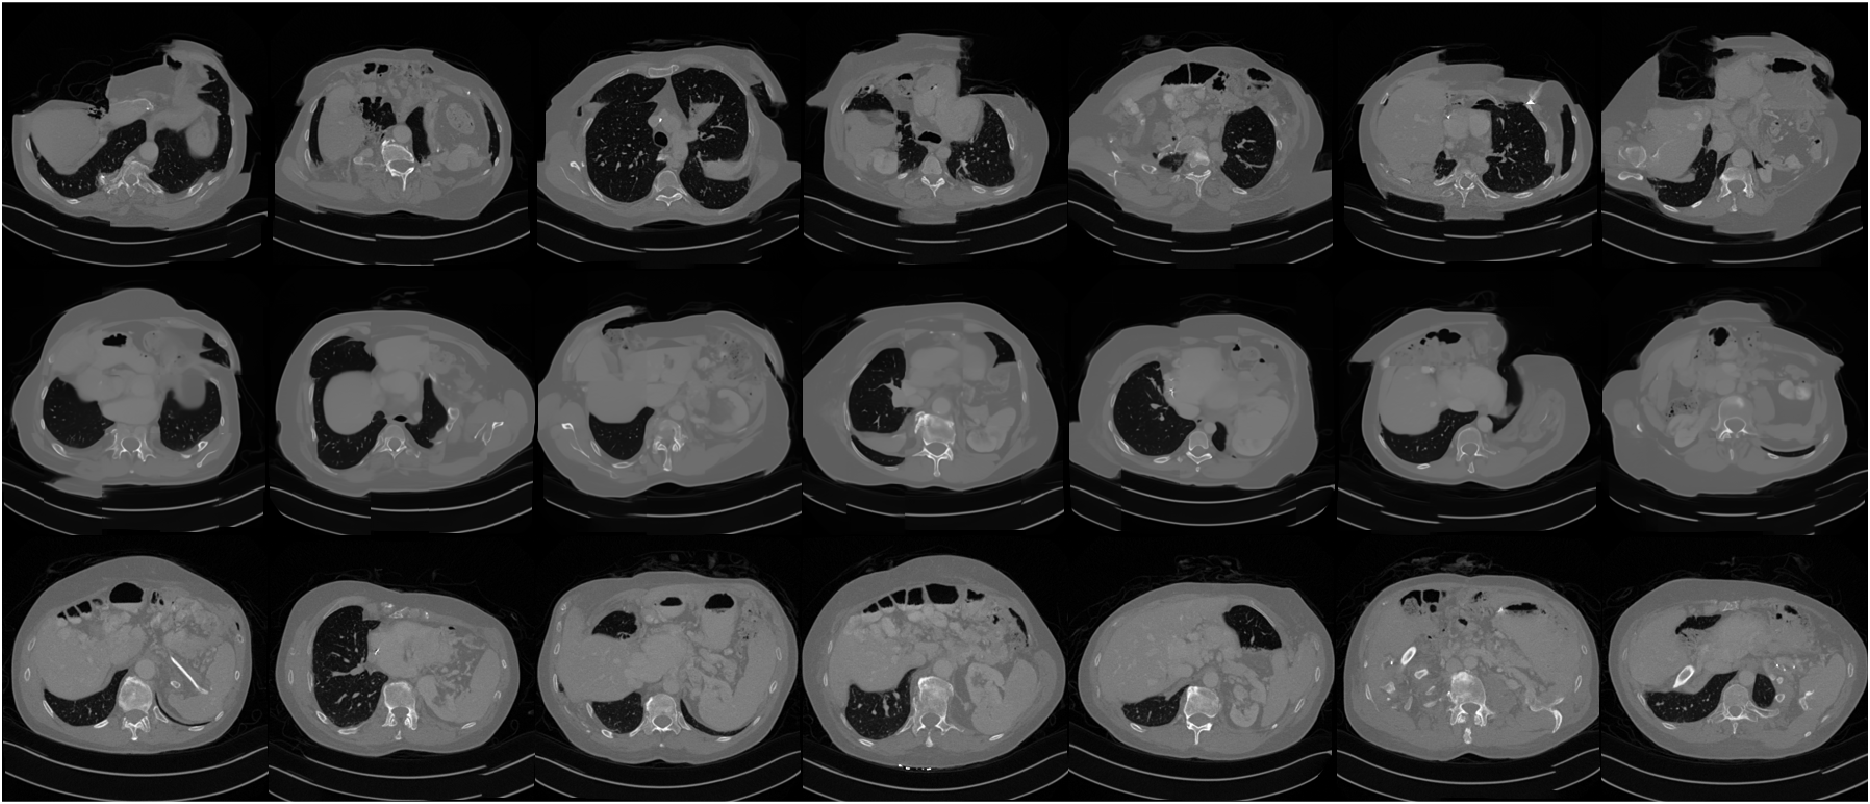

Refer to caption

Figure 5: Results of CT reconstruction. 60 views are used for the top two rows, 20 views are used for the bottom two rows. To better show contrast between organs, we use modified Hounsfield units (HU) in the top figure, while we use the same scale the images were trained on in the bottom figure.

In the bottom of Figure 5, some artifacts are present in the reconstructions obtained by the diffusion model methods, although they are more apparent in the whole image model than with PaDIS. The measurements are very compressed in this case, so it is very difficult for any model to obtain diagnostic-quality reconstructions; the baselines perform significantly worse in terms of quantitative metrics and exhibit severe blurring. In clinical settings, patient diagnosis are typically performed with CT scans consisting of hundreds of views. The top of Figure 5 shows that when 60 views are used, our proposed method yields a much better reconstruction without artifacts. Nevertheless, we show the potential of our proposed methods to reconstruct images from very sparse views with a decent image quality, which could be potentially used for applications such as patient positioning.

Figures A.1, A.2, A.3, and A.4 show additional inverse problem solving results.

Fig. A.1 shows additional example slices for CT reconstruction from 20 views.

Fig. A.2 shows additional example slices for CT reconstruction from 8 views.